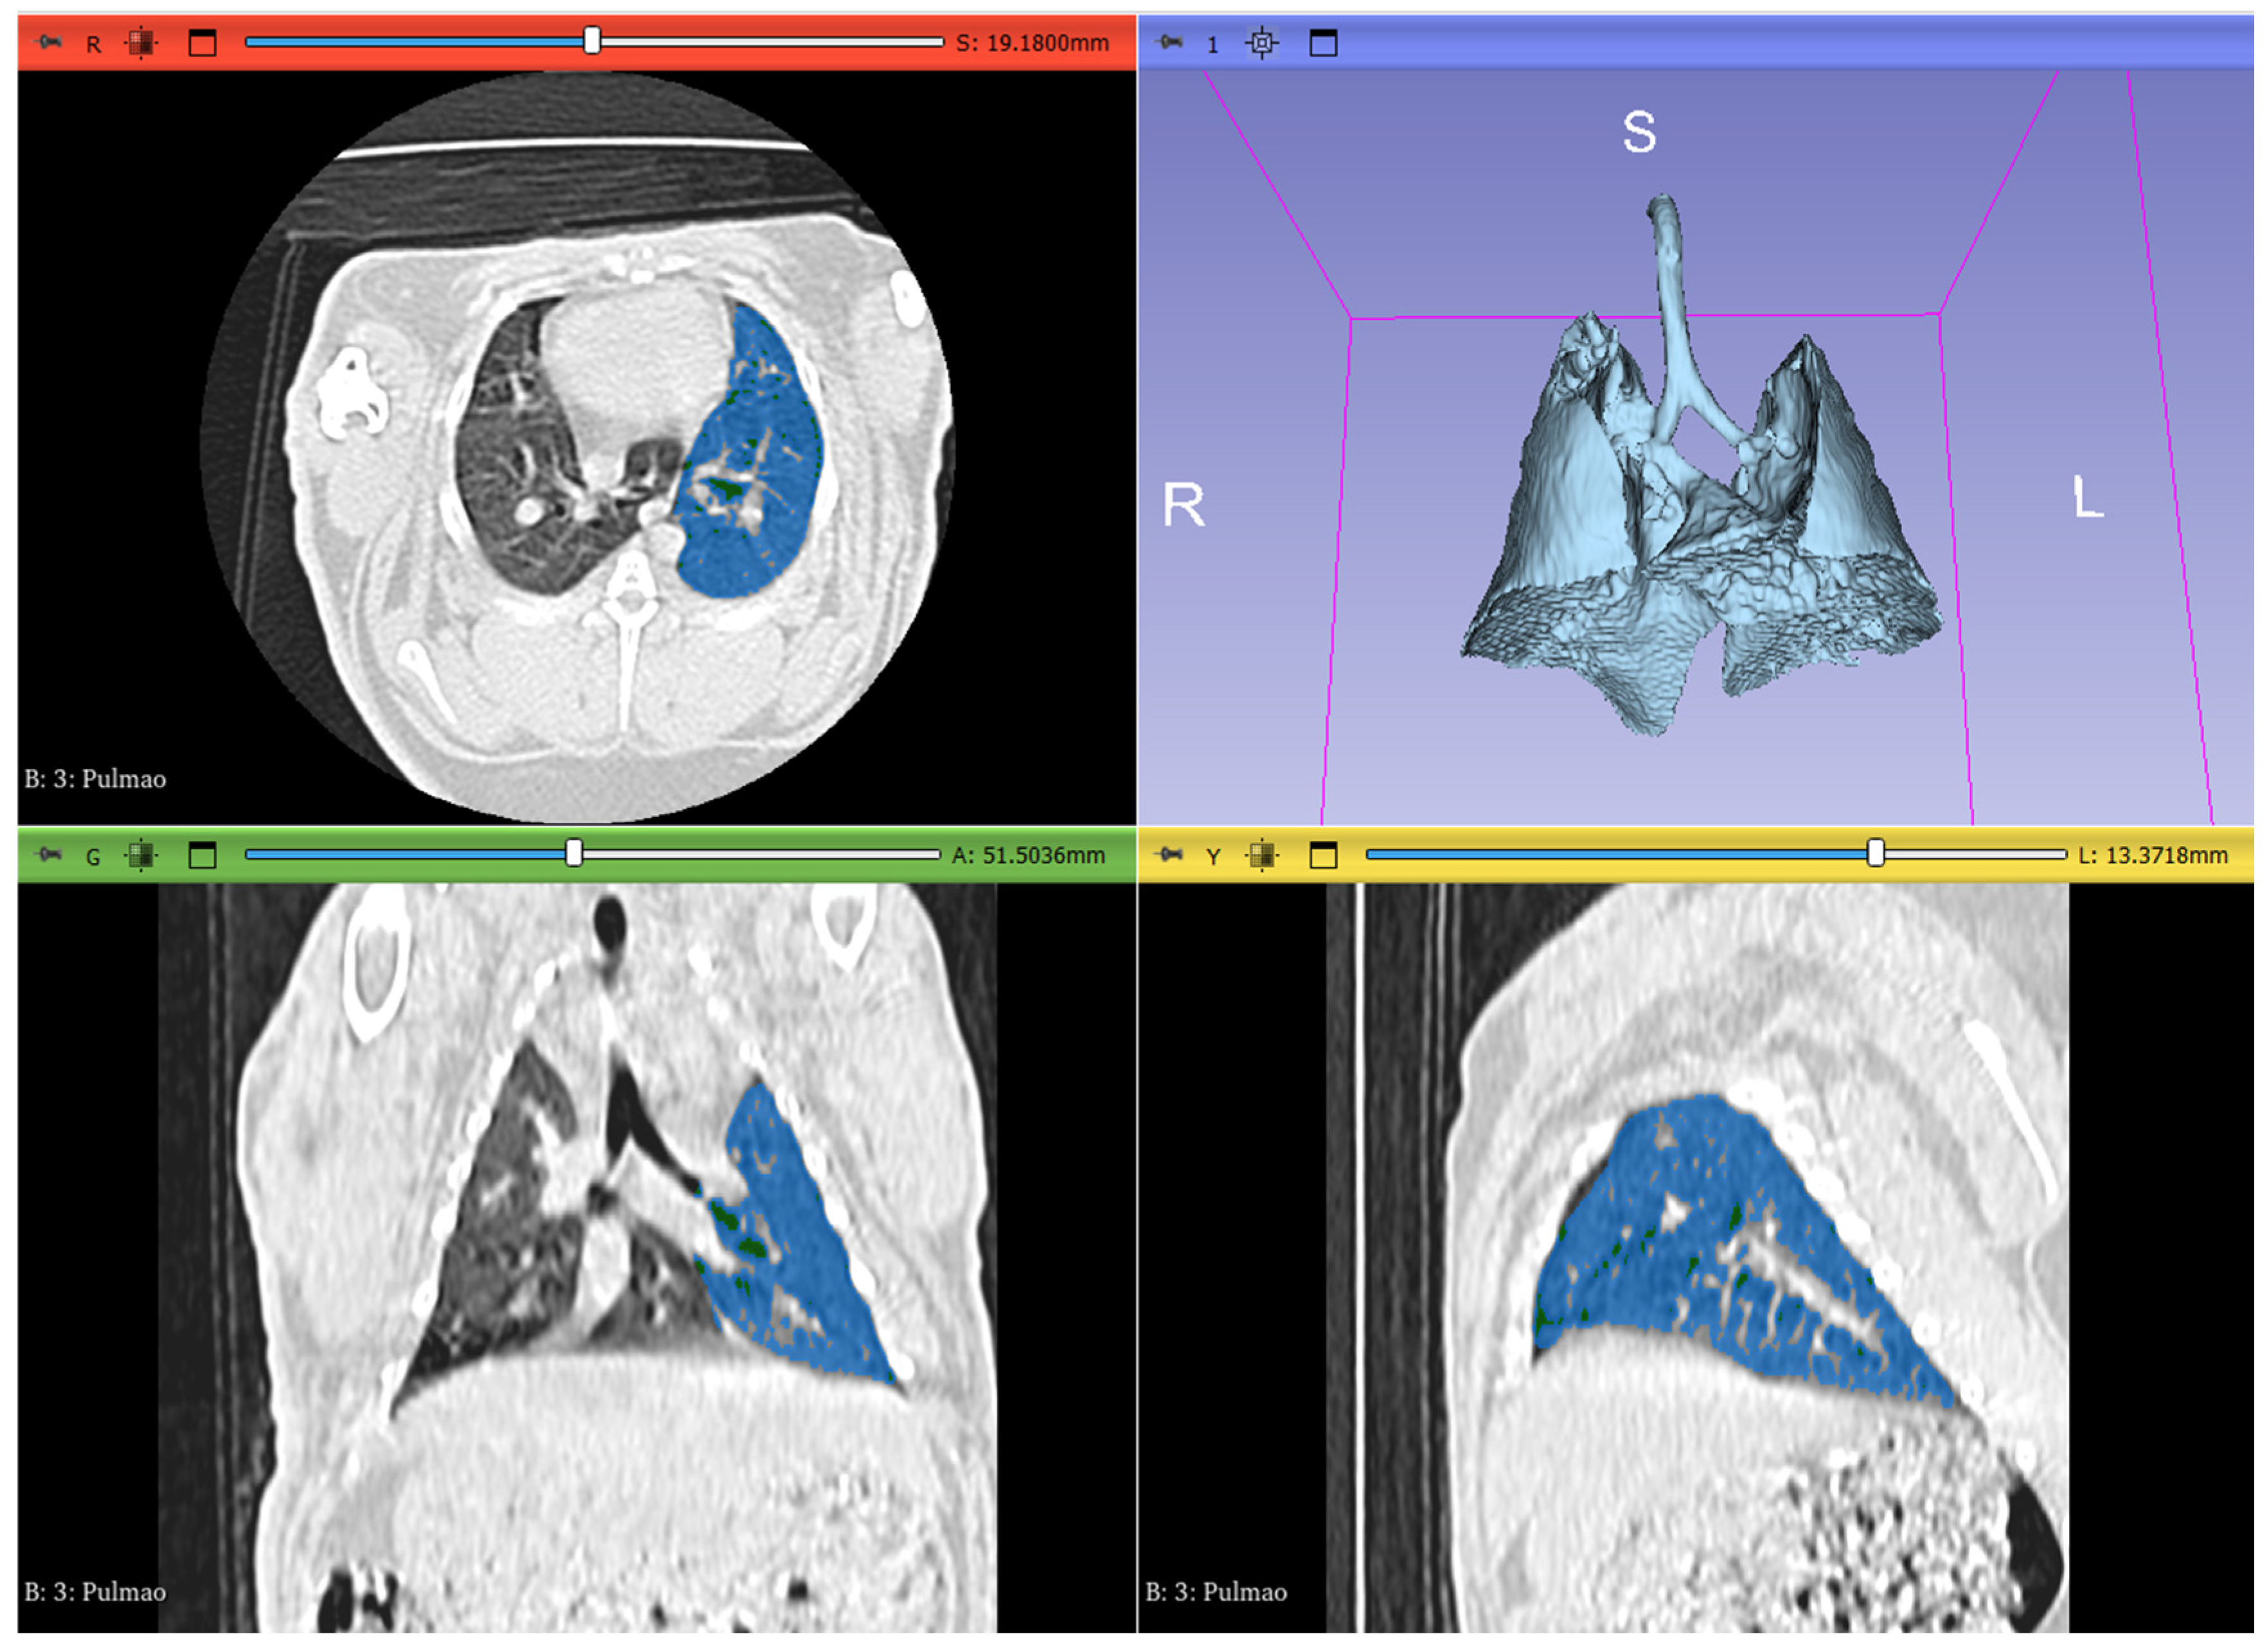

2.3. Image Analysis and Segmentation

- Slicer/SlicerLungCTAnalyzer 2024.

- Negroni, D.; Zagaria, D.; Paladini, A.; Falaschi, Z.; Arcoraci, A.; Barini, M.; Carriero, A. COVID-19 CT Scan Lung Segmentation: How We Do It. J. Digit. Imaging 2022, 35, 424–431. [CrossRef]